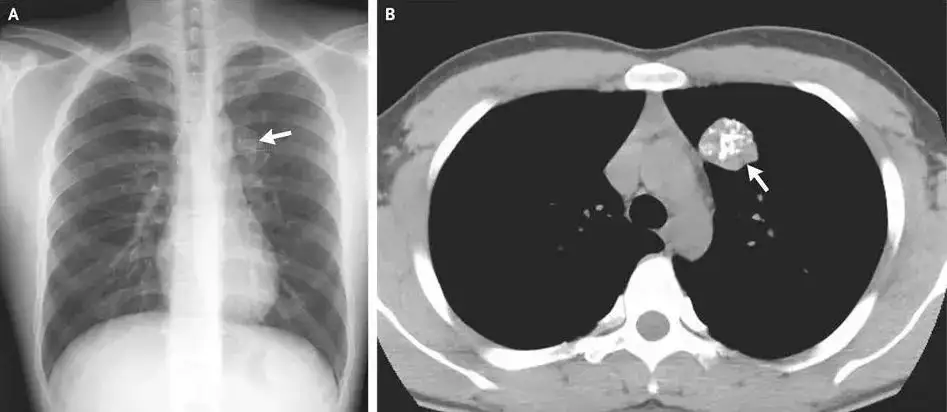

肺部钙化:一般来说,肺部的单个或少量钙化灶多为陈旧性病变遗留,通常无需特殊治疗,定期复查观察即可。但如果钙化灶较大或数量较多,伴有其他异常表现,如咳嗽、咳痰、咯血、胸痛等,则需要进一步检查。